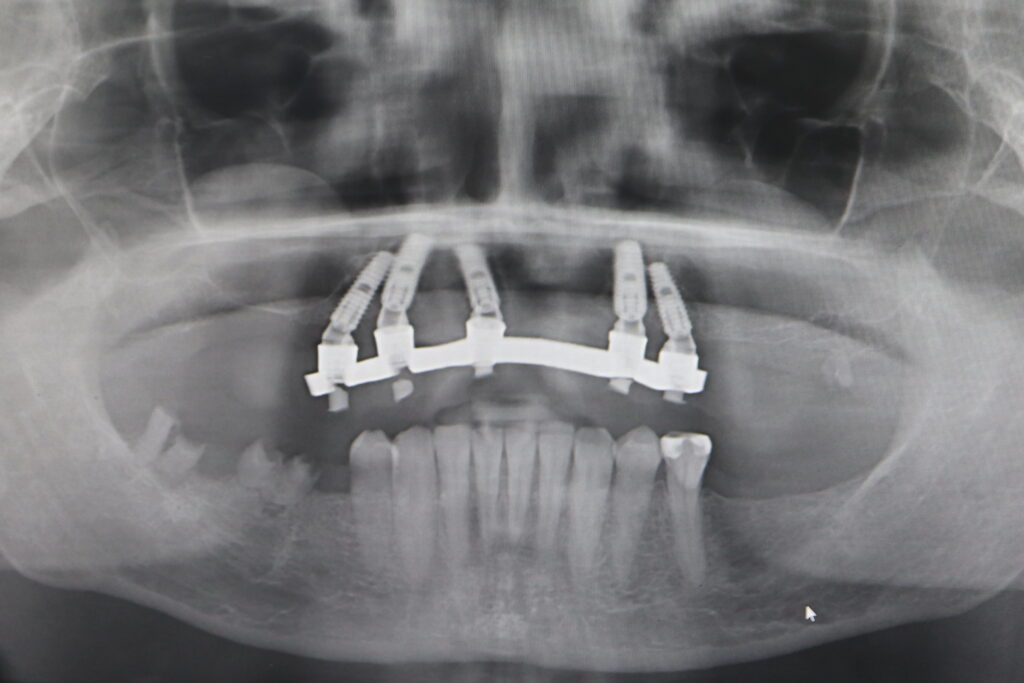

Процесс работы

Что было сделано:

На верхней челюсти были удалены зубы, которые находились в неудовлетворительном состоянии. Удалена киста в области зуба 2.1.

Установлены 5 имплантантов Megagen Anyone и сняты оттиски.

Спустя 5 дней на верхней челюсти зафиксирован протез из пластмассы, армированный металлической балкой из КХС (кобальт-хромовый сплав) с опорой на 5 дентальных имплантатов.

процесс тотальной имплантации

Это фото может содержать тяжелый для восприятия контент